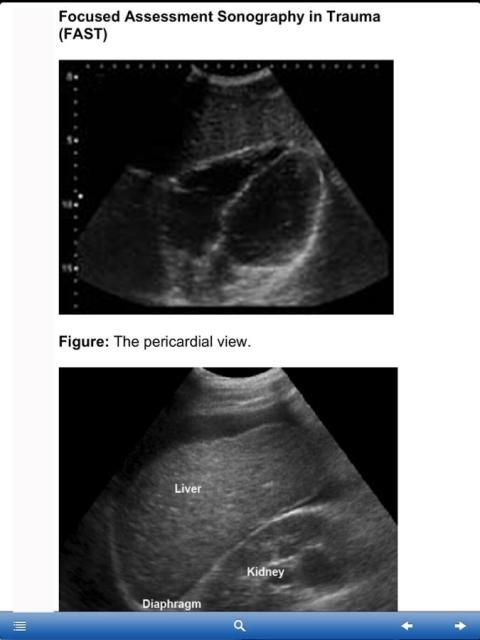

Основное внимание оценке Сонография Травма

Пожалуйста, ознакомьтесь с изображения на экране перед загрузкой.